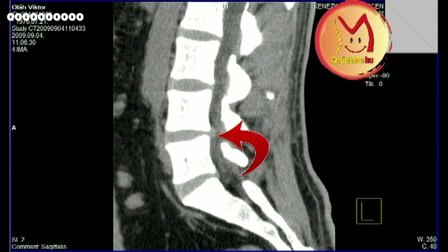

Szenzomotoros amnézia és a gerincsérv kapcsolata! www.gerincem.hu